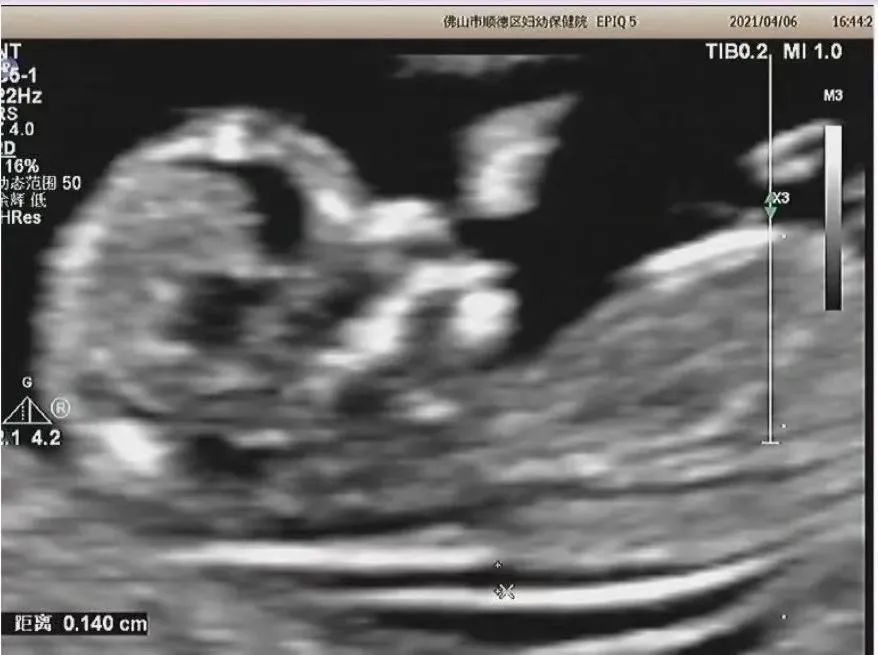

超声筛查:NT(颈项透明层)厚度检测可筛查80%的21-三体胎儿。